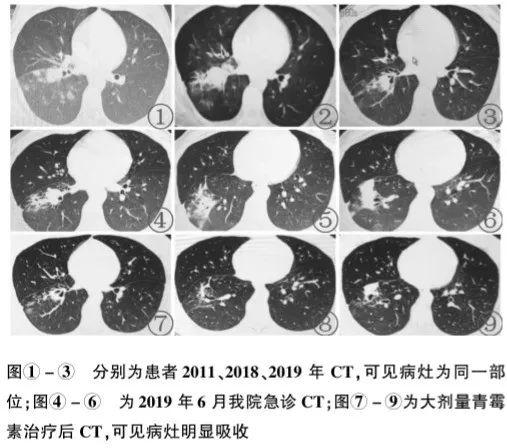

多数肺部放线菌病的影像学表现像一般的肺炎(图7)。

图7 肺部放线菌病影像学表现

图7 肺部放线菌病影像学表现部分时候,肺部放线菌病的影像学表现和肺癌类似(图8),做PET-CT都难以鉴别。